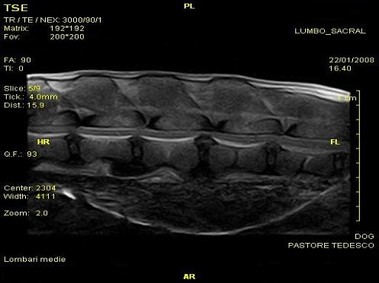

В настоящее время МРТ является наиболее предпочтительным методом визуализации любых мягких тканей, особенно для визуализации травм и патологий центральной нервной системы и суставов. Особенности Vet-MR позволяют использовать данный метод визуализации также в сфере ветеринарии.

Vet-MR специально разработана для визуализации небольших животных и является результатом внимания к деталям при разработке магнита, катушки и электронных компонентов, обеспечивая высокое качество экономически эффективной и простой в использовании МРТ в сфере ветеринарии.

- Высокое качество изображения